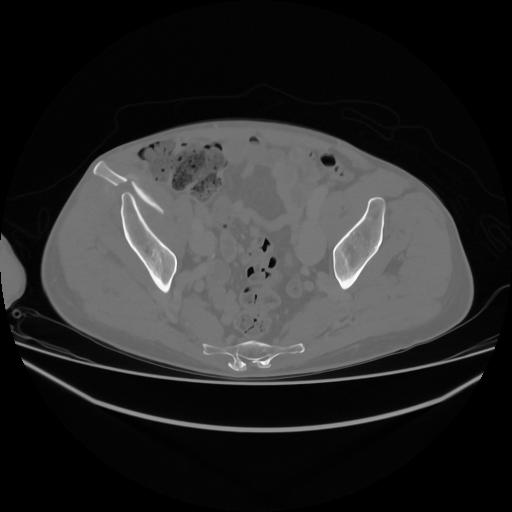

5 CUERPO,CE,Vol,1.0,CUERPO,,